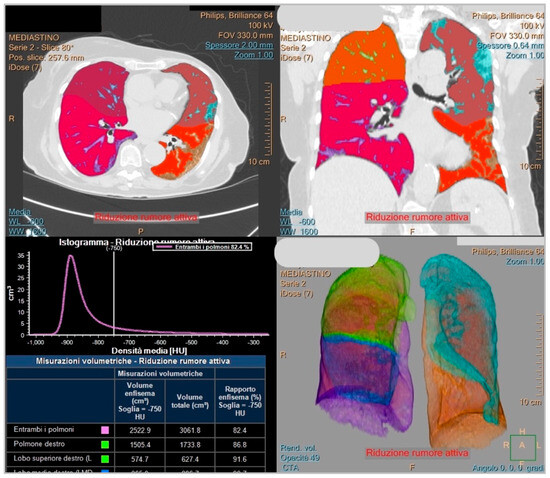

The second software used in this study is called Philips IntelliSpace Portal clinical application CT-COPD (Philips, Eindihoven, The Netherlands) computer tool. It is a semi-automatic software for lung segmentation; it was mainly used to measure the extent of the pulmonary emphysema in patients with chronic obstructive pulmonary disease (COPD). It enables us to set up a threshold of Hounsfield unit (HU) to quantify the lung parenchyma accordingly to the needs of the operator. In this study, the HU threshold chosen to establish the lung parenchyma affected by SARS-CoV-2 infection was set at -750, as proposed in other studies [8,18,19]. The SBQAS for this tool was performed by two blinded and trained radiographers (A.M, M.N), and the result was obtained by considering the percentage of the total lung parenchyma amount minus the extent of the percentage of aerated residual lung volume.

An example of the report obtained from Icolung and CT-COPD are, respectively, illustrated in Figure 2 and Figure 3.

Figure 3. This figure displays an example of a report from COPD (Philips, Eindihoven, The Netherlands).